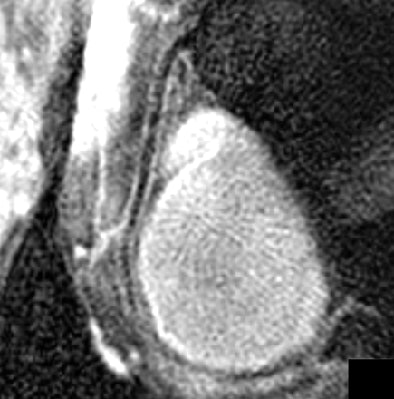

| Reformatted right coronary artery vessel wall images of a healthy 24-year-old man acquired with Cartesian k-space imaging (above) and radial k-space imaging (below). Image republished with permission of the American Society of Roentgenology ©, from AJR 2007; 188:70-74. Paul M. Bansmann, Andrew N. Priest, Kai Muellerleile, Alexander Stork, Gunnar K. Lund, Michael G. Kaul, and Gerhard Adam. |